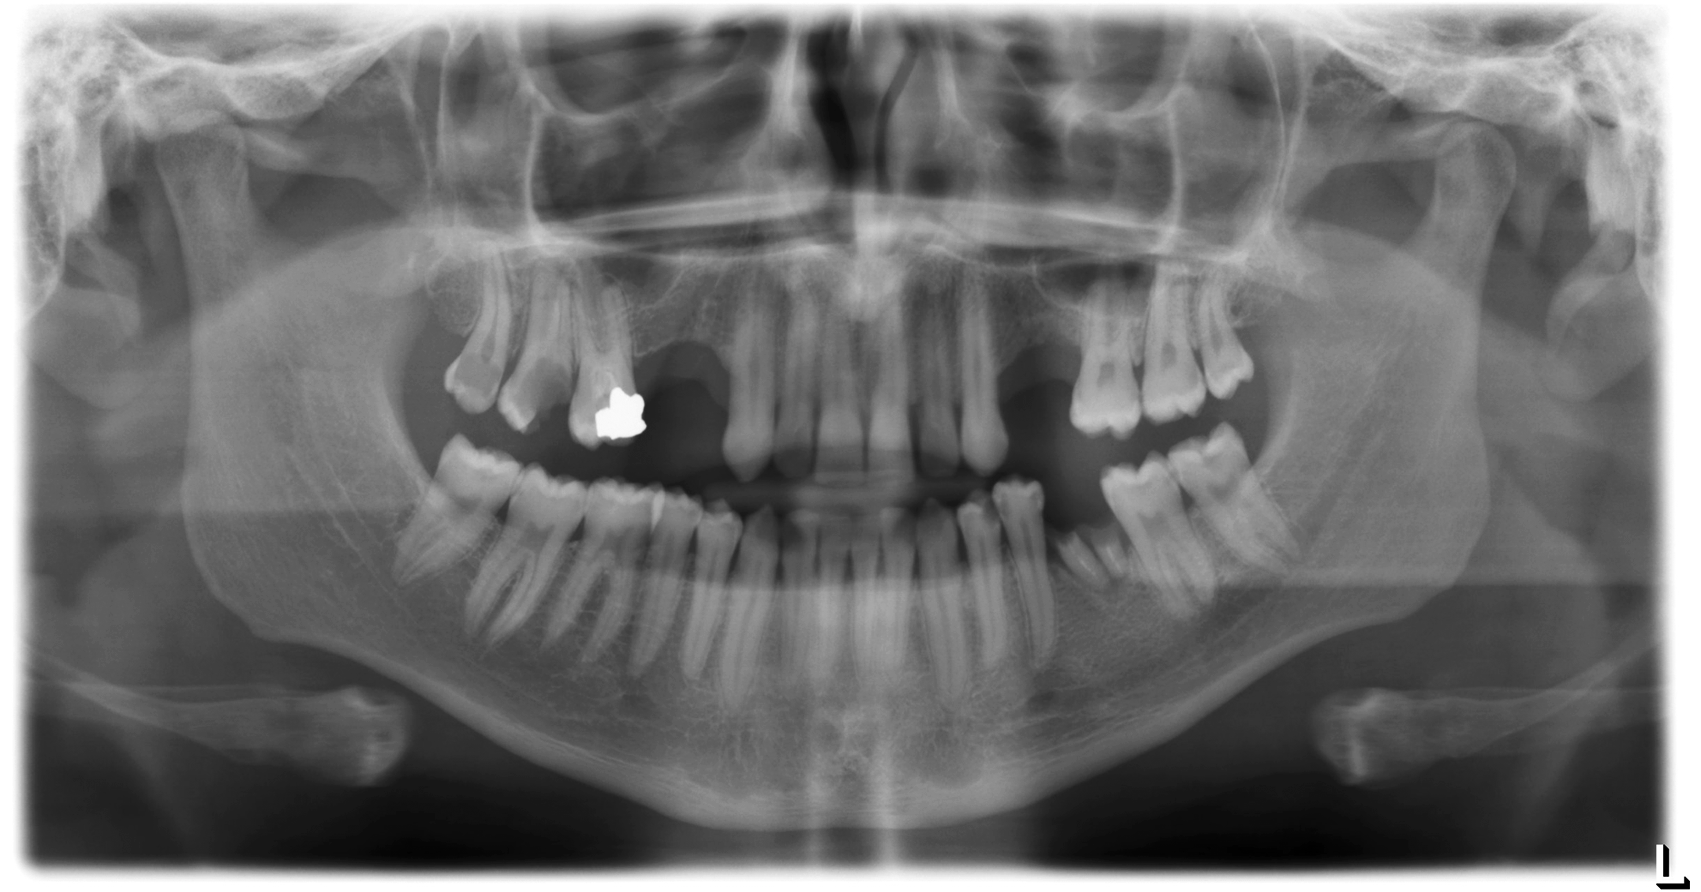

The integrated tooling allows the user to switch back and forth between the native X-ray image and the color-highlighted detections. This also makes it easy for the patient to understand the problem and the treatment plan.